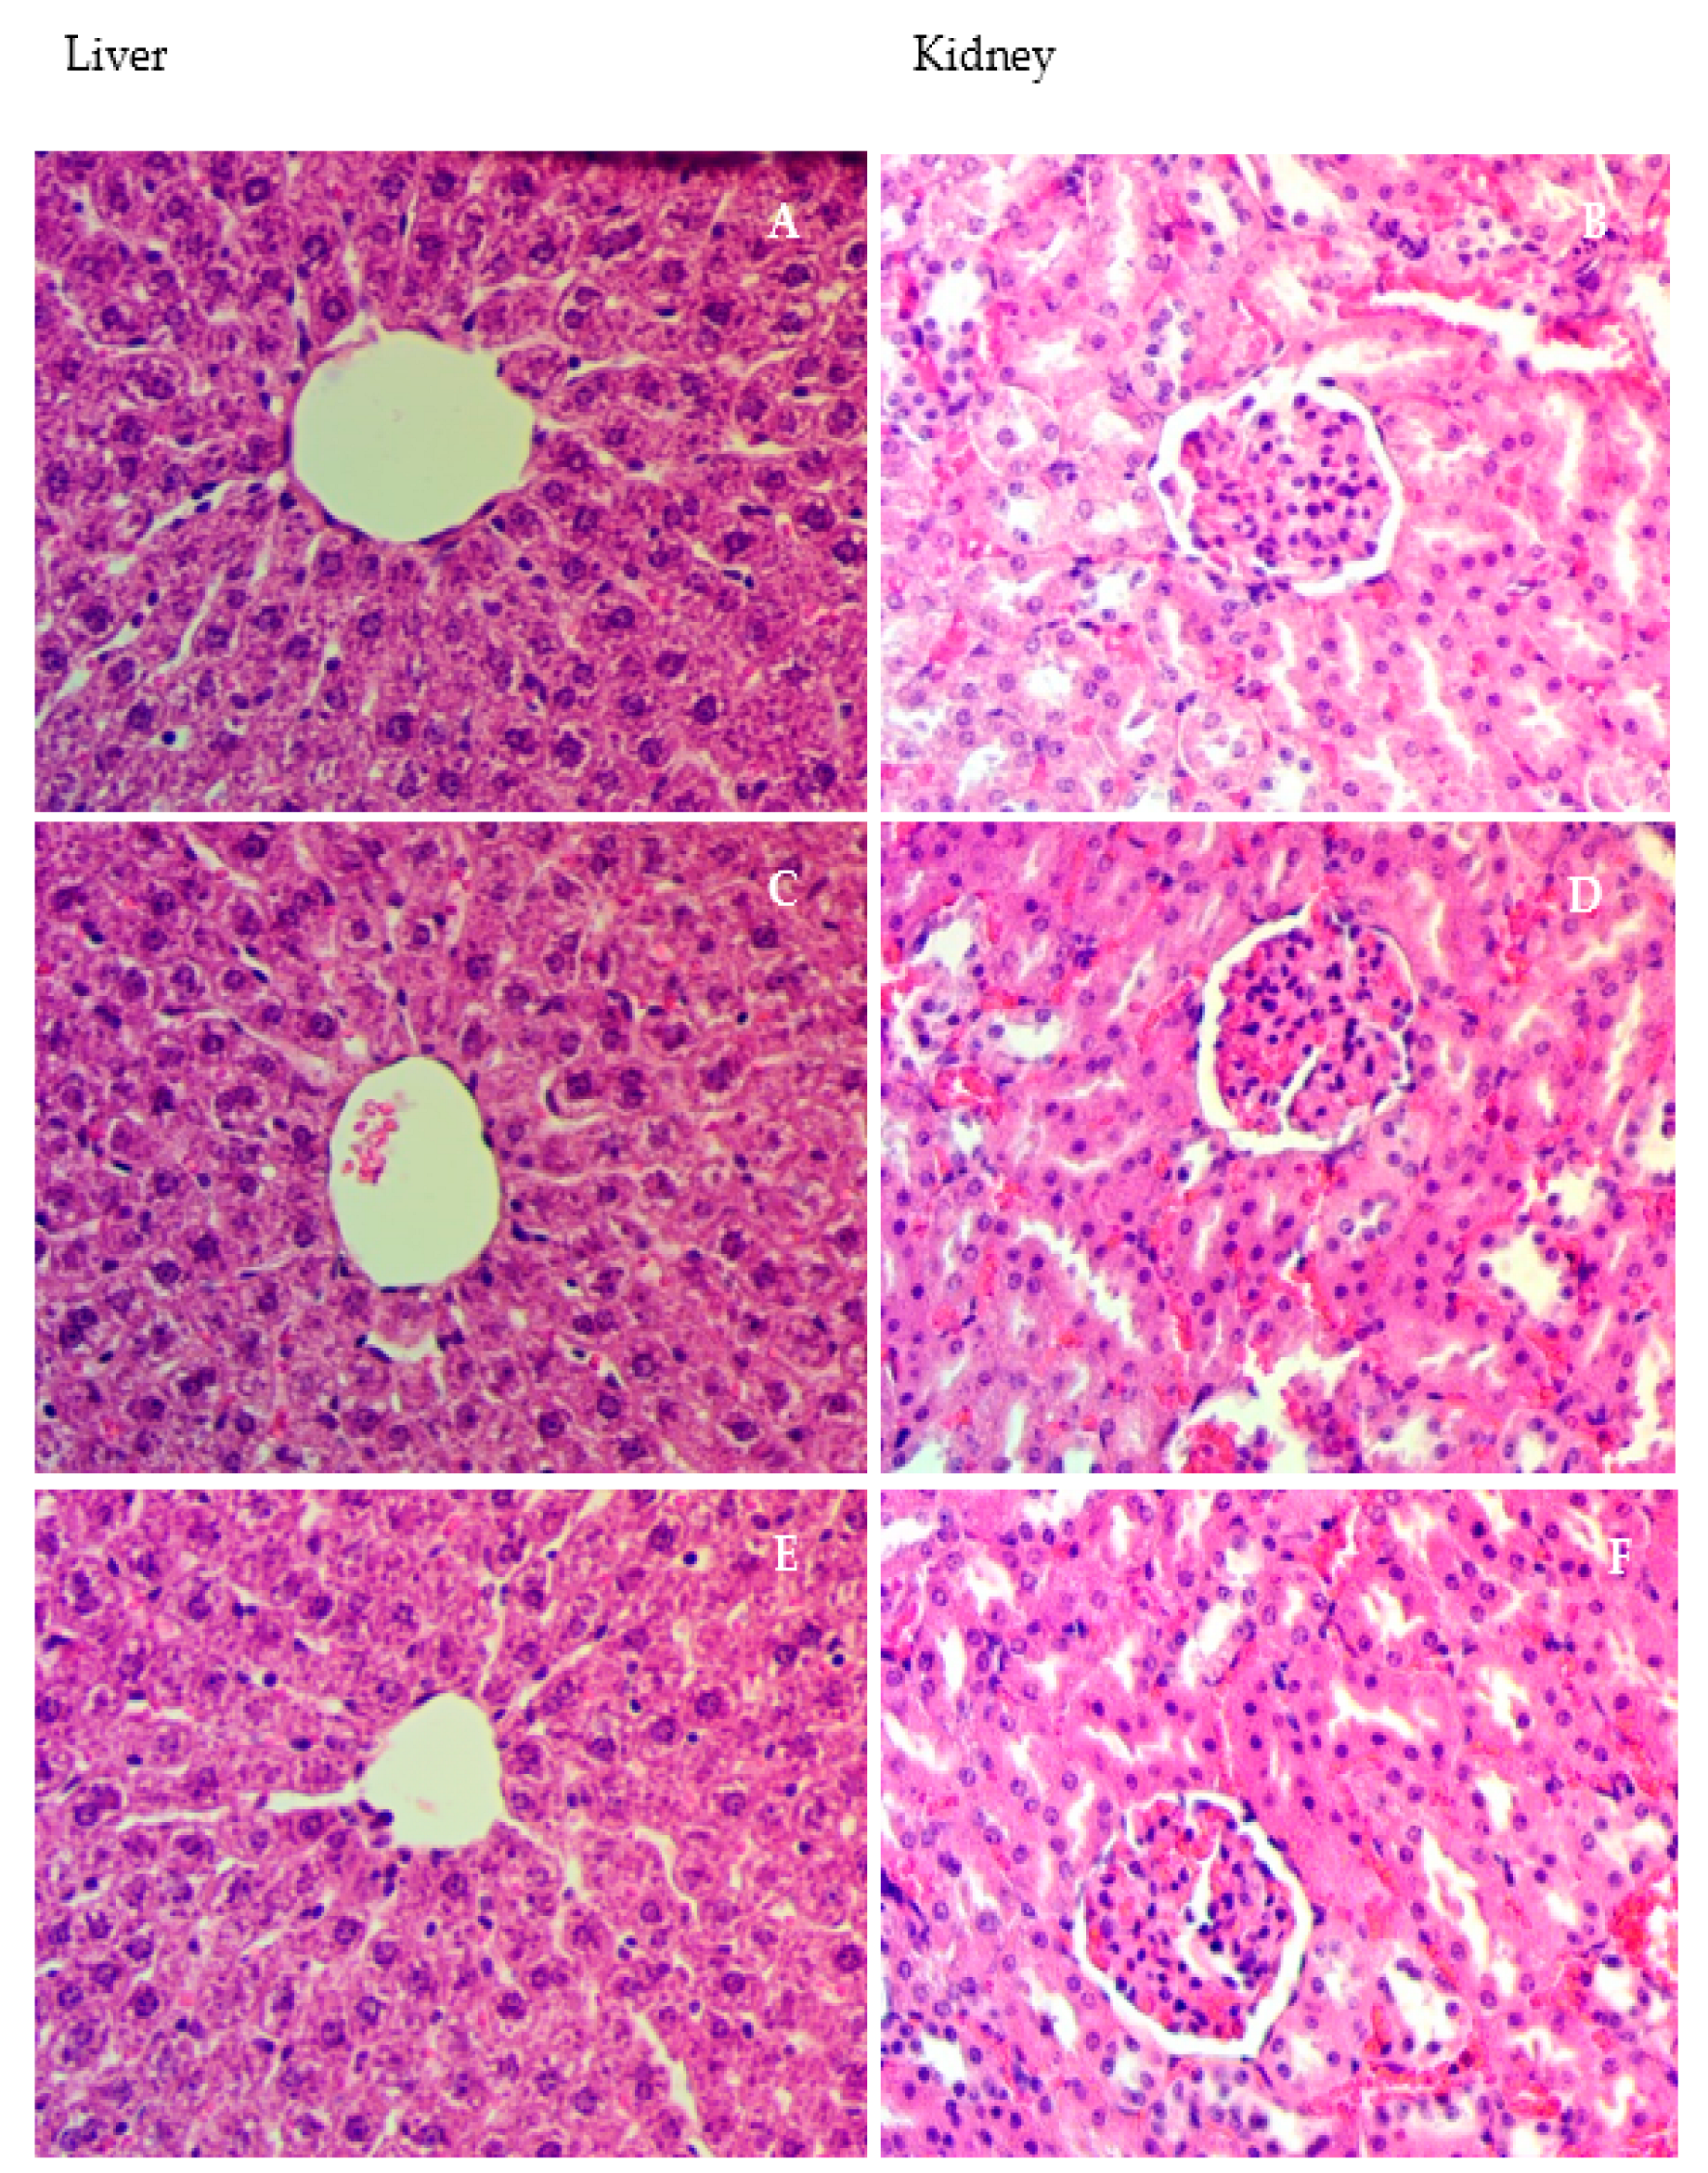

3.6. Microscopically Investigation of Liver

3.7. Immunohistochemically Staining of Hepatic Slices